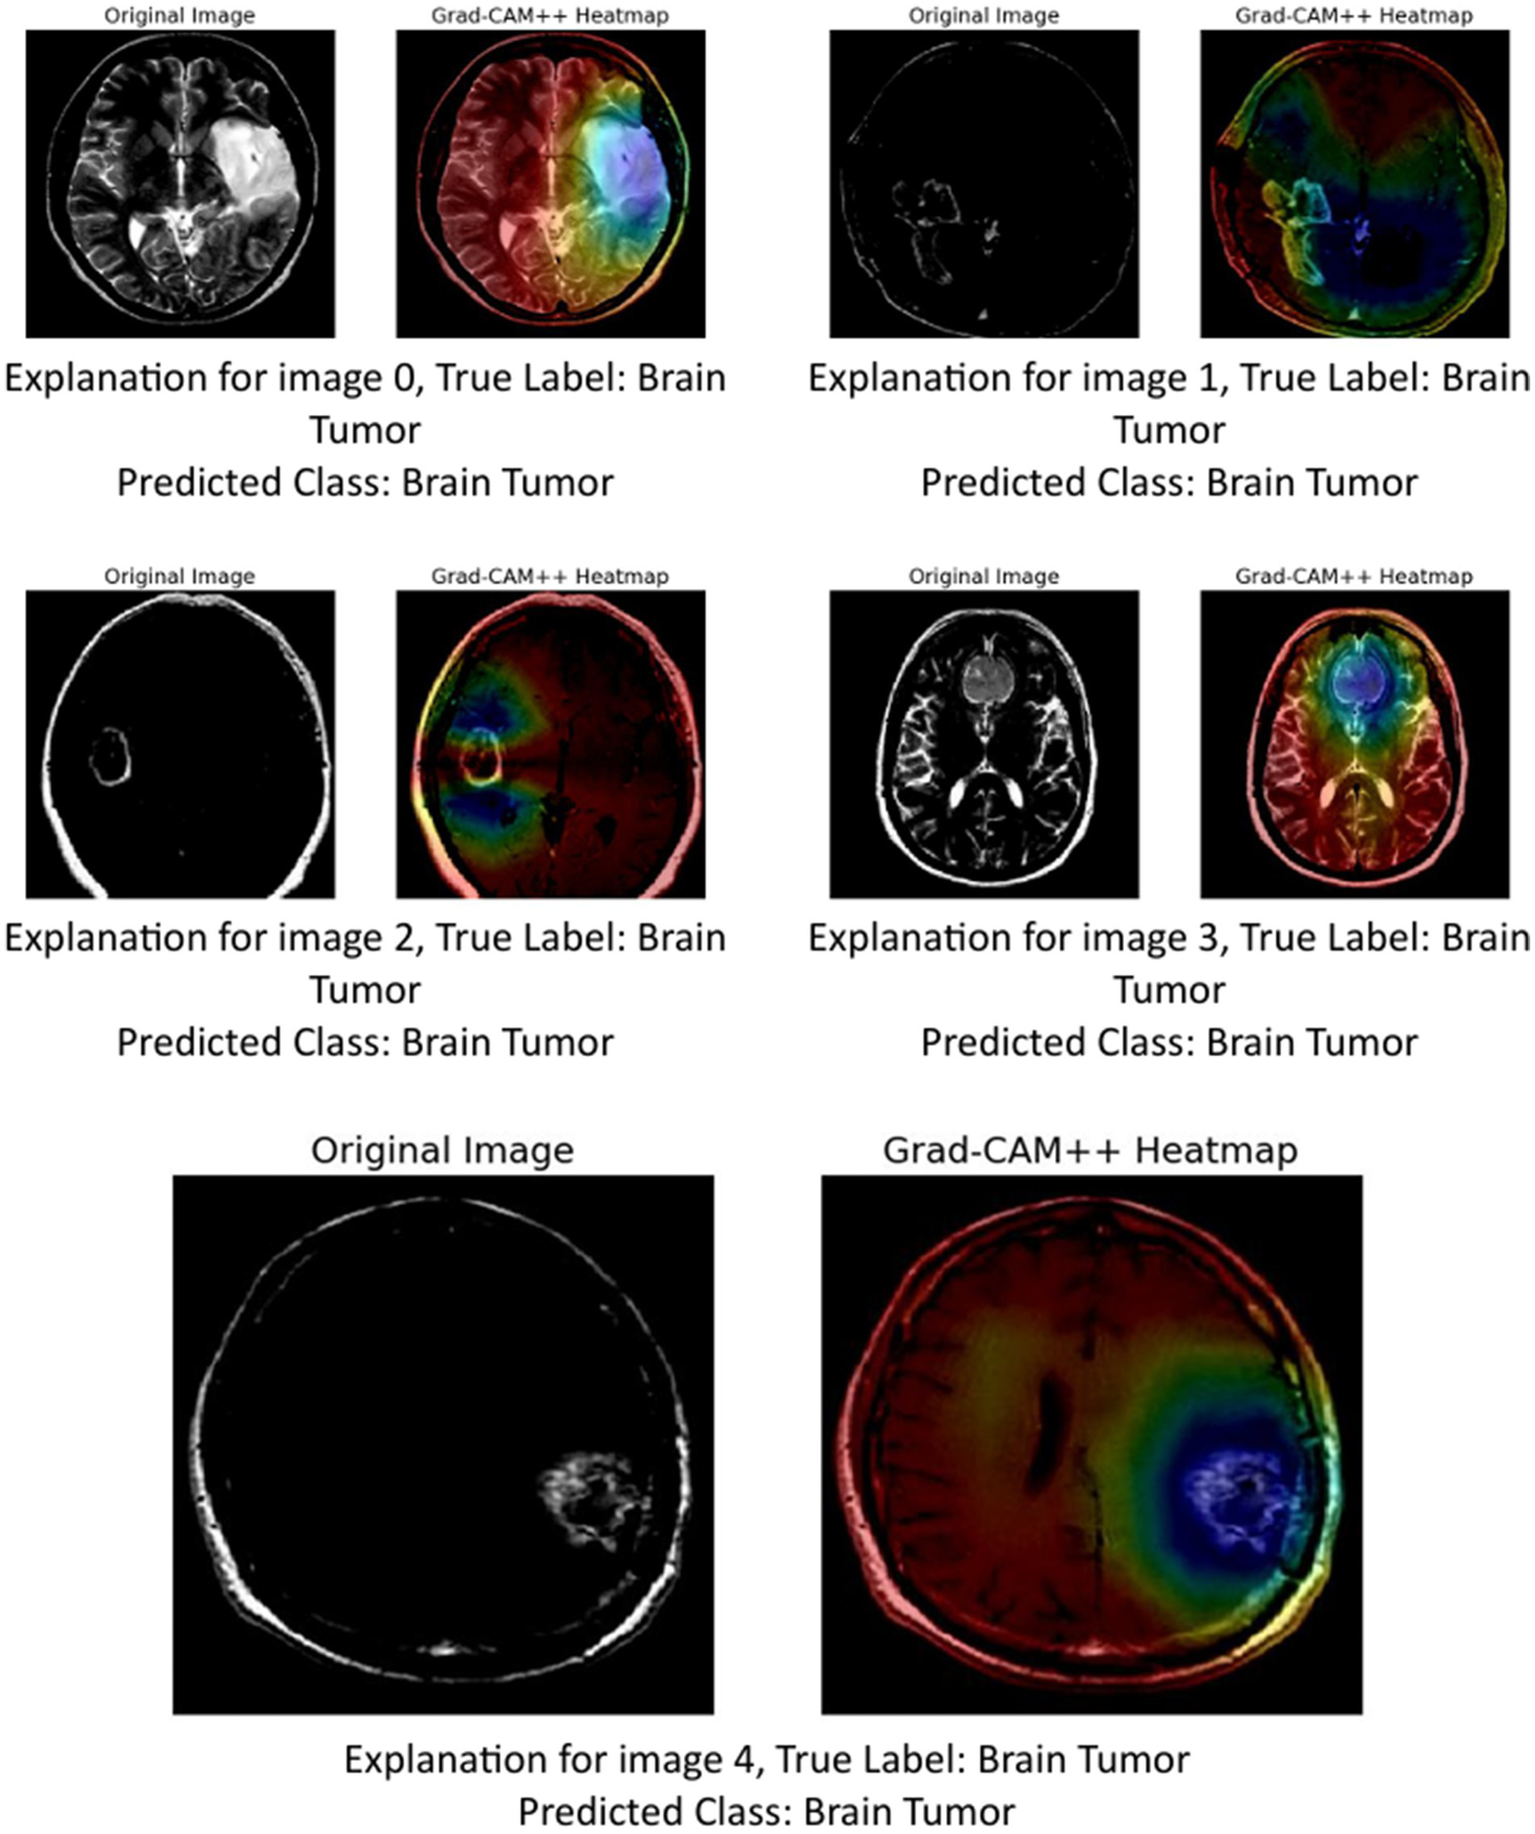

The provided image set presents a series of Grad-CAM++ visualizations applied to five brain MRI scans, who each diagnosed as having a brain tumor. These visualizations serve as an interpretability tool to understand the internal workings of deep learning models used in medical imaging. Grad-CAM++ (Gradient-weighted Class Activation Mapping++) is an enhancement over the original Grad-CAM technique, offering finer and more spatially precise localization of features that influence a model’s decision.

Grad-CAM++ improves upon Grad-CAM by considering higher-order derivatives of the output can coming the feature maps. This results in sharper and more reliable heatmaps, especially useful when multiple instances or small objects are present in an image (Chattopadhyay et al., 2022). In the context of medical imaging, such as MRI scans of brain tumors, Grad-CAM++ helps visualize which exact regions of the scan the model deems important for classification (Gao et al., 2023).

-

Image 0:

Original image: Displays a clear structure of the brain, including the tumor area.

Grad-CAM++ heatmap: The central region, where the tumor is visibly located, shows a high activation (in red-yellow), indicating that the model strongly relied in this area to identify the tumor.

Observation: The tumor boundary and surrounding tissue are highlighted effectively, demonstrating good interpretability.

Image 1:

Original image: Features a darker scan, but the tumor is discernible.

Grad-CAM++ heatmap: Activations are concentrated around the upper-mid portion of the brain, aligning well with the tumor location.

Observation: The model captures both the core of the tumor and some adjacent regions, suggesting sensitivity to contextual features.

Image 2:

Original image: A clean scan with a bright abnormal region.

Grad-CAM++ heatmap: Strong focus in the central part, slightly diffused around the tumor area.

Observation: Grad-CAM++ shows focused activation, but also includes surrounding regions, possibly indicating model consideration of surrounding tissues.

Image 3:

Original image: Exhibits distinct brain anatomy with a visible lesion.

Grad-CAM++ heatmap: High intensity near the center with tight boundary focus, particularly over the tumor.

Observation: Suggests that the model is highly accurate in pinpointing tumor locations, confirming the reliability of its internal decision logic.

Image 4:

Original image: Displays a well-formed tumor in the lower right area.

Grad-CAM++ heatmap: The highest activation is located precisely over the tumor mass, with minimal distraction in other areas.

Observation: The result here shows a nearly perfect match between the medical region of interest and the model’s focus.

These visualizations demonstrate (Figure 13) that Grad-CAM++ offers high-resolution, interpretable insights into CNN-based tumor detection models. It not only reveals the correct regions of interest (ROIs) within the MRI scans but also provides medical professionals with a visual validation of model predictions, which is essential for building trust in AI-assisted diagnostics. The consistent overlap between activated areas in the heatmaps and the actual tumor locations supports the use of Grad-CAM++ as a credible explainability method in medical imaging research.

Figure 13

GRAD-CAM++ visualization.